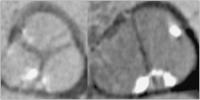

Abbildung 3: Aortenklappe. Linksseitig trikuspide Aortenklappe (Mercedes-Stern), rechts bikuspide Aortenklappe. Beide Klappen weisen geringe Kalzifikationen auf (helle Spots).